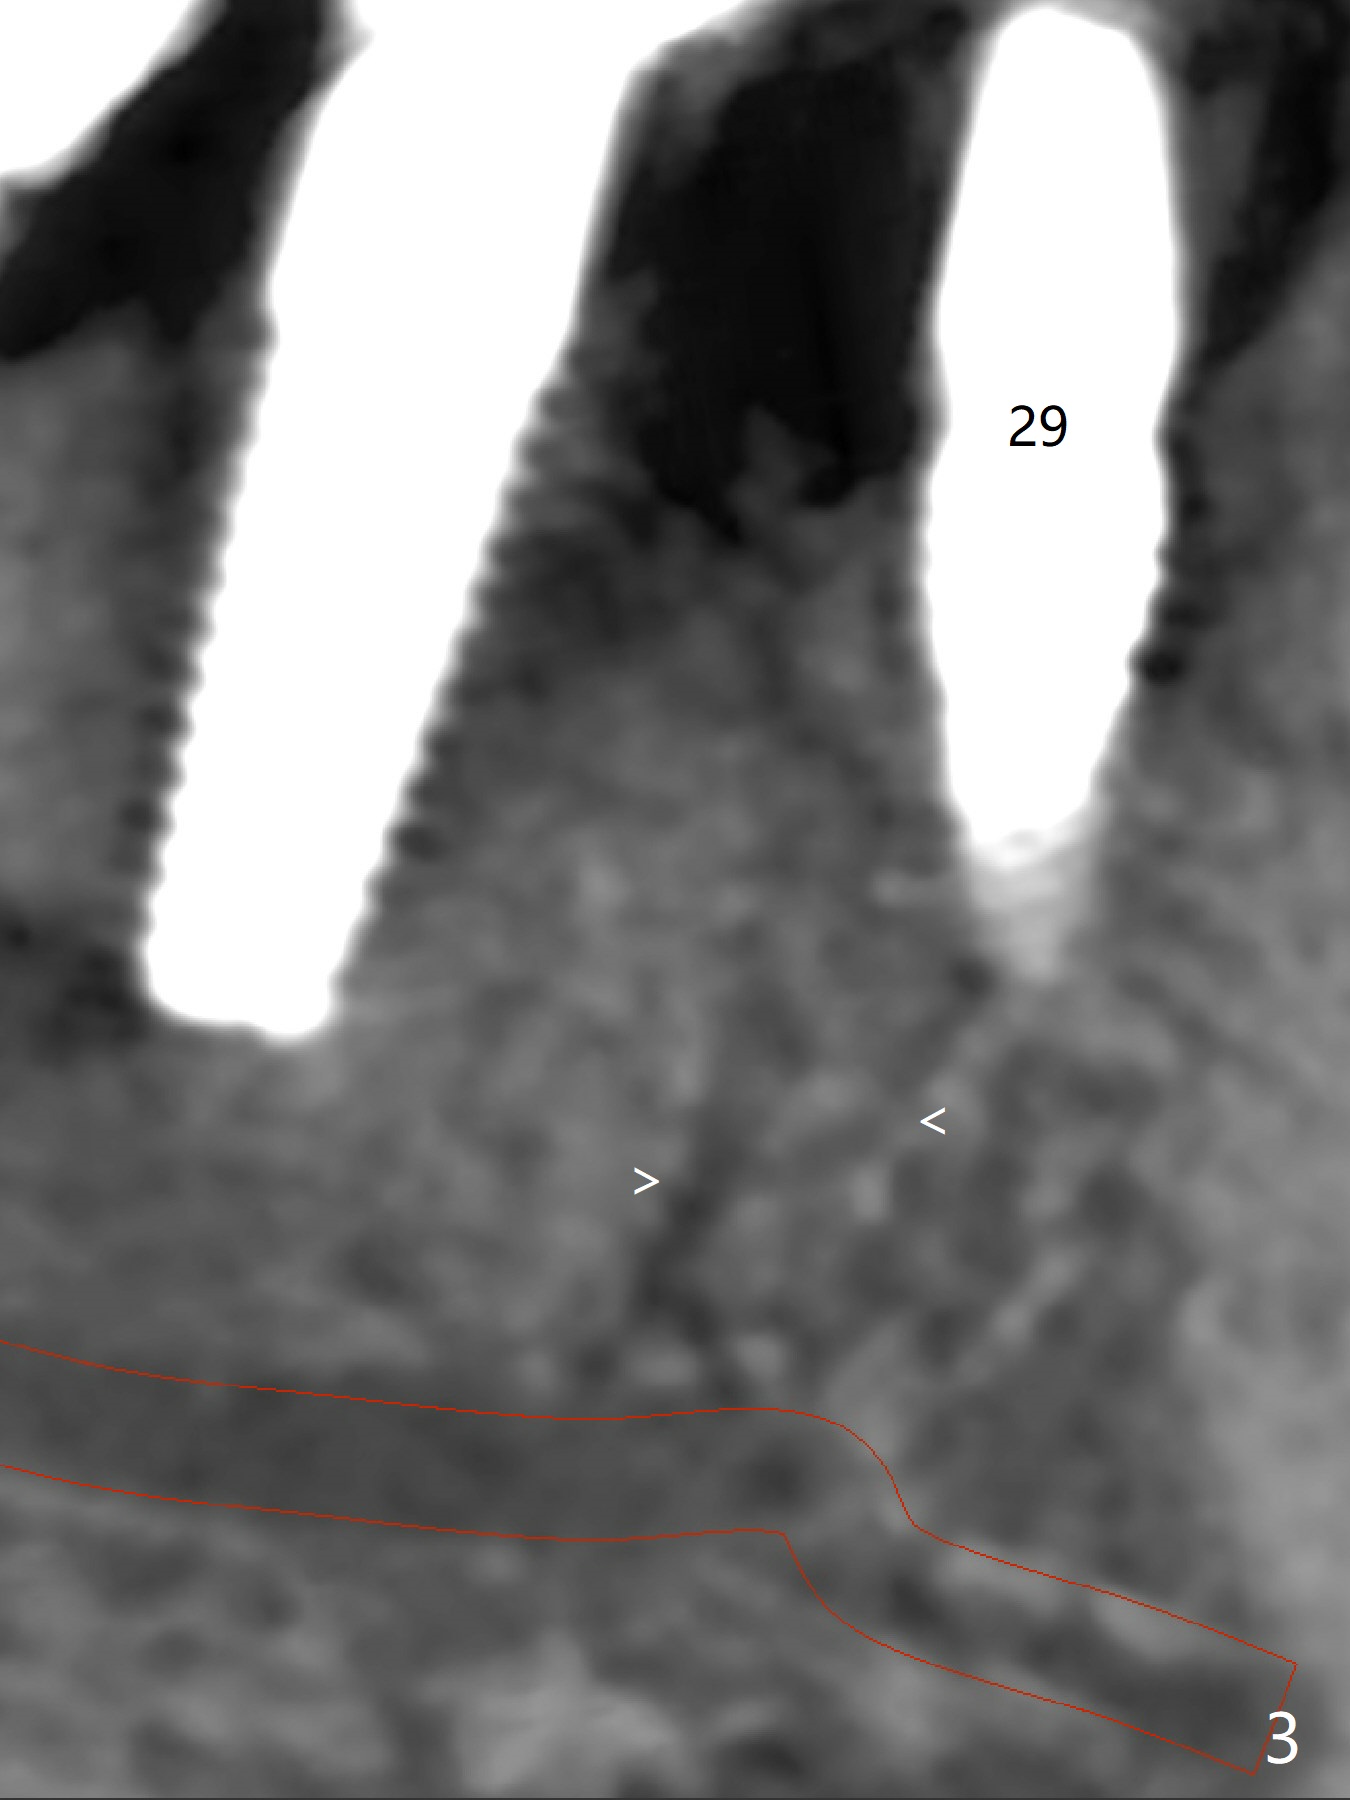

Six months post implant removal and bone graft, the patient returns for #29 implant placement with guide. With Lidocaine and Septocaine each carpule (infiltration), the patient experiences pain when the last drill used is ~ 2 mm short of designed depth. To make sure to have lingual subcrestal placement and avoid the Mental Loop, a 3.5x8.5 mm implant is placed (Fig.1,2 (3 mm shorter than the design)). Immediately postop CBCT (sagittal section) shows that the osteotomy probably hits the branch from the Mental Nerve (Fig.3 <). The coronal portion of the implant is covered with apparently grafted bone (Fig.4 <; bone density ~ 1,000 Hounsfield units; L: lingual). The implant will be loaded longer than 4 months due to unfavorable crown/implant ratio.